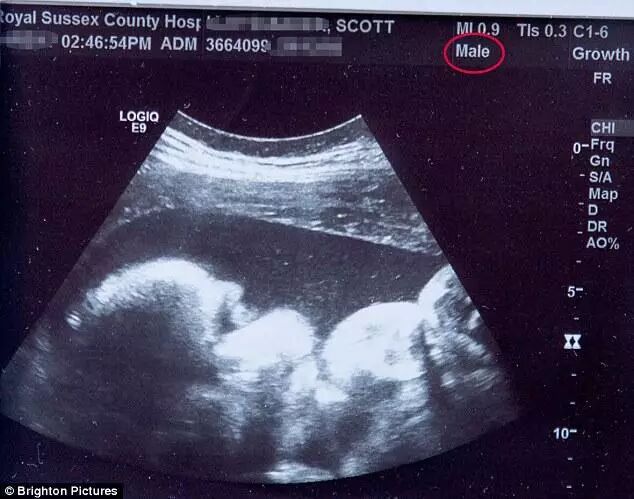

在怀孕23周做产检的时候,产检报告上Sara的父母一栏清楚的写着男性,Scott对此非常满意,实际上他也非常自豪能做一名父亲,